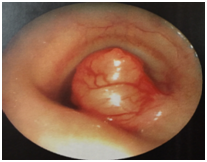

A 42-year-old male with a history of Diabetes mellitus type of 14 years of evolution, systemic arterial hypertension (ASH) of recent diagnosis that started 2 years ago, presenting dyspnea of medium effort, as well as dry cough and intermittent pharyngodynia. In December of 2013, a hemoptysis was added, so his hospitalization was decided and he was discharged on the third day. Bronchoscopy was performed by pulmonologist, finding a tumor between the 3rd and 4th tracheal ring, obstructing 80% of the lumen of which (Figure 1) a biopsy was taken, which was reported as cystic adenoid carcinoma with a cribiform and tubular pattern. They requested our assessment to perform a low tracheotomy we request assessment by performing a low tracheostomy. CT Computed tomography of the neck is requested, observing at the level of the first tracheal rings rounded lesion, attached to the wall which measures 13x13x1mm, being limited to the tracheal light occupying 85% of the same, without data of infiltration of adjacent tissues with important enhancement when applying contrast medium (Figure 2) (Figure 3). Evaluated by surgical oncology in March 2014 and May 2014 to perform neck exploration and resection of the 1st to 3rd tracheal ring with tracheal plasty, finding tumors from the 1st to the 3rd tracheal ring with free edges according to the transoperative examination, 4 days in the ICU with adequate evolution without need of ventilatory support, without presenting data of respiratory difficulty, with adequate evolution, it is discharged without the need of additional treatment. I do not consider it necessary to administer chemo-radiotherapy, the last tomographic control in November 2014 without evidence of tumoral activity, asymptomatic.

Figure 2 Contrast CT scan of the neck of the neck.